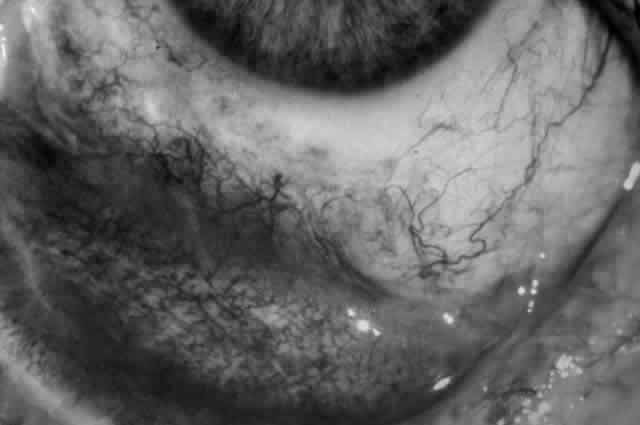

Clinically, the ocular disease in cicatricial pemphigoid (OCP) may present unilaterally in the form of a chronic, recurrent catarrhal conjunctivitis, but it eventually becomes bilateral. Subepithelial fibrosis is characteristic of stage 1 of OCP (Fig. 7). Stage 2 shows fornix foreshortening (Fig. 8), and symblepharon formation is the hallmark of stage 3 (Fig. 9). Stage 4, end-stage disease, is characterized by ankyloblepharon and surface keratinization (Fig. 10). Obstruction of the lacrimal ductules and meibomian gland ducts eventually produces an unstable tear film and progressive sicca syndrome, but it is to be emphasized that OCP is not a dry-eye syndrome until late in the disease course.20 Trichiasis and entropion occur because of the subepithelial fibrosis, with eventual keratopathy, corneal neovascularization, and corneal ulceration and scarring.20

Fig. 7. Stage 1 cicatricial pemphigoid, with cicatrizing conjunctivitis, and fine striae-type areas of subepithelial fibrosis, but without evidence of shrinkage of the conjunctiva.

Fig. 8. Stage 2 cicatricial pemphigoid, with fornix foreshortening and subepithelial fibrosis without frank symblepharon formation.

Fig. 9. Stage 3 of an eye affected by cicatricial pemphigoid. The conjunctival “shrinkage” continued and a frank symblepharon developed.

Fig. 10. Stage 4 cicatricial pemphigoid. Progressive shrinkage of the conjunctiva resulted in extreme trichiasis and distichiasis and keratopathy, with compromise of meibomian ductules and lacrimal ductules and the production of a totally dry eye.